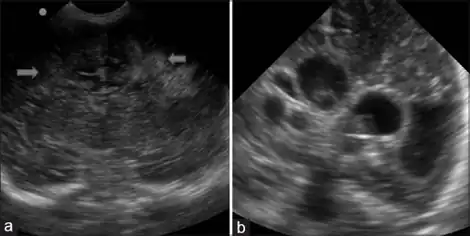

Periventricular leukomalacia (PVL) is a form of white-matter brain injury, characterized by the necrosis (more often coagulation) of white matter near the lateral ventricles.[1][2] It can affect newborns and (less commonly) fetuses; premature infants are at the greatest risk of neonatal encephalopathy which may lead to this condition. Affected individuals generally exhibit motor control problems or other developmental delays, and they often develop cerebral palsy or epilepsy later in life. The white matter in preterm born children is particularly vulnerable during the third trimester of pregnancy when white matter developing takes place and the myelination process starts around 30 weeks of gestational age.[3]

As previously noted, there are often few signs of white matter injury in newborns. Occasionally, physicians can make the initial observations of extreme stiffness or poor ability to suckle. The preliminary diagnosis of PVL is often made using imaging technologies. In most hospitals, premature infants are examined with ultrasound soon after birth to check for brain damage. Severe white matter injury can be seen with a head ultrasound; however, the low sensitivity of this technology allows for some white matter damage to be missed. Magnetic resonance imaging (MRI) is much more effective at identifying PVL, but it is unusual for preterm infants to receive an MRI unless they have had a particularly difficult course of development (including repeated or severe infection, or known hypoxic events during or immediately after birth).[5] No agencies or regulatory bodies have established protocols or guidelines for screening of at-risk populations, so each hospital or doctor generally makes decisions regarding which patients should be screened with a more sensitive MRI instead of the basic head ultrasound.